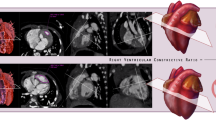

Of the cohort of 38 patients who underwent imaging of the thorax, a subset of 20 individuals underwent dedicated cardiac MRI assessment for myocardial fat. Nine of the 20 individuals (45%) showed intramyocardial fat on the fat–water separation sequence (Fig. 1). Within the LV, the intramyocardial fat was more commonly present in the septal wall (n = 9, 45%) compared to other walls of the LV (P = 0.0029). The RV was involved less often than the LV (n = 6 and n = 9, respectively). Within the RV, the RV free wall was the most common location for the intramyocardial fat (n = 6, 30%), however this was not significantly different from other RV locations (P > 0.05). Intramyocardial fat distribution patterns were variable and included endocardial, midwall, epicardial, transmural, diffuse, and focal (Table 2). Some individuals had more than one pattern of intramyocardial fat within the same LV segment. In the LV, intramyocardial fat was most commonly located in an endocardial distribution. In the RV, intramyocardial fat most commonly was present diffusely within the RV free wall.

Cardiac MR images depicting intramyocardial fat in a 21-year-old female with Proteus syndrome. (a) Short axis cine image of a midventricular slice shows some areas of low signal intensity within the right ventricular (RV) trabeculae (arrowhead) and RV side of the interventricular septum (arrow) secondary to areas of chemical shift artifact caused by the presence of small areas of fat in the myocardium. Short-axis cardiac optimized multi-echo Dixon water (b) and fat (c) separation images of a mid-ventricular slice. (b) Short axis water image of the mid heart shows areas of intramyocardial fat as low signal intensity, for example within the RV trabeculae (arrowhead) and along the RV side of the interventricular septum (arrow). The fat image (c) shows areas of high signal intensity compatible with fat within the RV trabeculae (arrowhead) and RV endocardial side of the interventricular septum (arrow). (d) CT image of the chest confirms areas of fat within the RV side of the interventricular septum and right ventricular free wall of the heart (arrows). Patterns of intramyocardial fat are depicted on (e–g). Short axis water image (e) of a mid LV slice shows areas of midwall (thick arrow) and subendocardial (arrowhead) fat in the left ventricle as areas of low signal intensity. There is also fat involving the RV free wall (thin arrow). A corresponding fat image (f) shows the midwall (thick arrow), subendocardial (arrowhead), and RV wall fat (thin arrow) as areas of high signal intensity. Note that the subendocardial fat which is difficult to appreciate on the water image because of its similar signal intensity to the blood pool is very obvious on the fat image. (g) Short axis fat image of the mid LV shows a transmural area of high signal intensity corresponding to transmural fat within the septal wall (arrow). (h) Short axis fat image of a mid LV slice shows areas of fat as high signal intensity in several distributions: epicardial in the inferior wall (thin arrow), endocardial on the RV side of the interventricular septum (thick arrow) and endocardial on the LV side of septal wall (arrowhead).

Chest CTs were obtained in 34 individuals and also evaluated for the presence of intramyocardial fat (Fig. 1, Table 4). 16 of the 34 individuals, which included seven of the nine individuals with intramyocardial fat on cardiac MR, also had a chest CT. However, intramyocardial fat was missed on CT in one of these seven individuals by both readers who agreed this was most likely due to cardiac motion on the non-gated chest CT study. There were a total of 18 patients who only had chest CTs and no dedicated cardiac MRI to assess for intramyocardial fat. Evaluation of these 18 individuals who only had chest CTs for intramyocardial fat only detected one individual with intramyocardial fat. Thus, evaluation of the chest 34 chest CTs only detected a total of 7 (21%) cases of intramyocardial fat.

There was no statistically significant difference among any of the cardiac functional parameters in the individuals with intramyocardial fat compared to those without (Table 3). The average LVEF of the individuals who underwent cardiac MR was normal (60 ± 5) with only one individual (female, age = 10 years-old) who had intramyocardial fat that was associated with a mildly decreased LVEF of 53% and mild diffuse hypokinesis without a focal regional wall motion abnormality. No wall motion abnormalities were found in any of the other individuals. Only three individuals received gadolinium and only one individual had a small patch of subendocardial late gadolinium enhancement in the apical lateral wall, however there was no associated wall motion abnormality or decreased function.

In this study, we were able to further define the prevalence of cardiothoracic imaging findings in Proteus syndrome. Intramyocardial fat was common (45%) on cardiac MRI and its severity had no association with age. Although present in many places in both ventricles, the intramyocardial fat was always present in the septal wall. This intramyocardial septal wall fat is on the mild end of a spectrum of abnormal fat growth that includes the myocardial septal lipoma described within the clinical diagnostic criteria for Proteus syndrome (Table 1) at the more severe end of the spectrum. Interestingly, intramyocardial fat was also detected on the routine, non-cardiac gated chest CTs about half of the time (21%). This illustrates the importance of looking at the heart on routine chest CT exams, but also confirms that chest CT is an imperfect technique for intramyocardial fat detection as it missed cases detected by cardiac MRI. The intramyocardial fat does not appear to correlate with wall motion abnormalities or significantly impact LV function. Although a previous study reported arrhythmia (right bundle branch block) associated with intramyocardial fat in Proteus syndrome25, we observed no arrythmia associated with the presence of intramyocardial fat or any other adverse cardiac complications.

As Proteus syndrome is an overgrowth syndrome, we hypothesize that this intramyocardial fat may represent overgrowth of areas of physiologic intramyocardial fat that has been well described in healthy individuals. In healthy individuals, intramyocardial fat is commonly seen in the RV up to 85% of the time, but is only present in the LV or in both ventricles < 20% of the time26,27. Thus, Proteus syndrome differs by commonly having intramyocardial fat in both ventricles, with LV predominance over the RV. However, intramyocardial fat in Proteus syndrome is associated with no wall motion abnormality, a feature it shares with the intramyocardial fat present in healthy individuals. Unlike Proteus syndrome, pathologic conditions with intramyocardial fat tend to have associated ventricular chamber enlargement, dysfunction and wall motion abnormalities. These include arrhythmogenic RV cardiomyopathy (ARVC), healed myocardial infarction, dilated cardiomyopathy, and Duchenne’s muscular dystrophy. It should be noted that myocardial fat is no longer part of the diagnostic criteria for ARVC28. Further follow-up of the individuals with intramyocardial fat will be necessary to characterize its behavior over time and determine if it behaves similarly to a hamartomatous anomaly or more similarly to a fatty neoplasia.